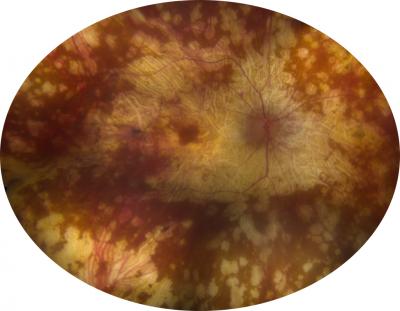

A work accident leaves a woman blind in one eye. As she copes with the loss, within months the vision in the other, previously uninjured eye begins to blur, and the eye becomes red and inflamed.

The rare eye condition, known as sympathetic ophthalmia, occurs when vision is lost in one eye through injury or multiple surgeries, and the body's overactive immune system attacks the remaining healthy eye. Left untreated, a person can become completely blind.